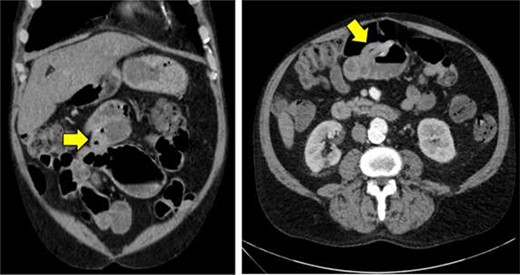

Double balloon enteroscopy revealing a 3 cm mass located in the distal jejunum/proximal ileum.

Given the patient’s anemia, melena and small bowel thickening, the patient was referred for upper and lower endoscopies, neither of which revealed the etiology of the patient’s symptoms. A pill endoscopy was also performed to evaluate the small intestine, though this was also unremarkable. The patient therefore underwent a double balloon enteroscopy, which was significant for a 3 cm small bowel mass located in the distal jejunum/proximal ileum (Fig. 2). The mass was biopsied and concerning for an adenocarcinoma. As a subsequent staging workup was negative for distant metastasis, the patient was taken for an exploratory laparotomy and small bowel resection. At the time of surgery, it was noted that the small bowel mass was located within an undiagnosed Meckel’s diverticulum (Fig. 3). The resected specimen was sent to pathology, which was significant for a moderately to poorly differentiated adenocarcinoma arising from a small bowel diverticulum, which was invading through the muscularis propria and into subserosal soft tissue with lymphovascular invasion (Fig. 4). The patient was therefore diagnosed with a Stage IIB (T4, N0) small bowel adenocarcinoma. After resection, the patient’s post-operative course was unremarkable, and he was discharged home on post-operative day 3. He was referred to medical oncology and is now receiving adjuvant capecitabine with oxaliplatin. As the patient’s resected specimen displayed negative margins, after completing the standard of care chemotherapy protocol, he will undergo active surveillance in accordance with the National Comprehensive Cancer Network guidelines.